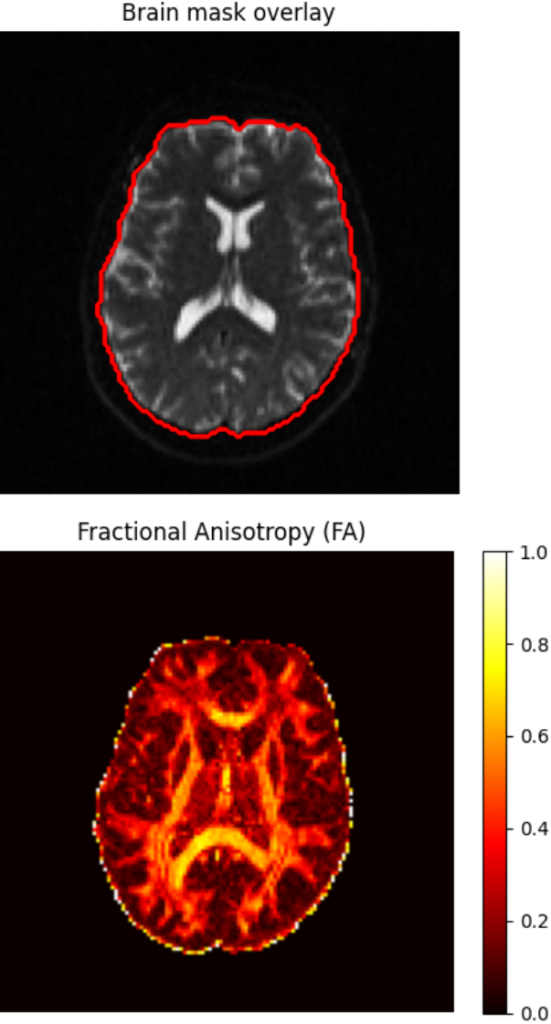

Example workflow demonstrating library installation and diffusion tensor fitting to compute a Fractional Anisotropy (FA) map. The streamlined interface requires minimal configuration to produce standard diffusion metrics.

Self-supervised denoising via Patch2Self (DIPY) and deep learning-based brain extraction using HD-BET, with support for both single-subject and batch processing.

3. Diffusion Tensor Imaging (DTI)

Diffusion tensor modeling using DIPY to compute standard microstructural maps including Fractional Anisotropy (FA) and Mean Diffusivity (MD).